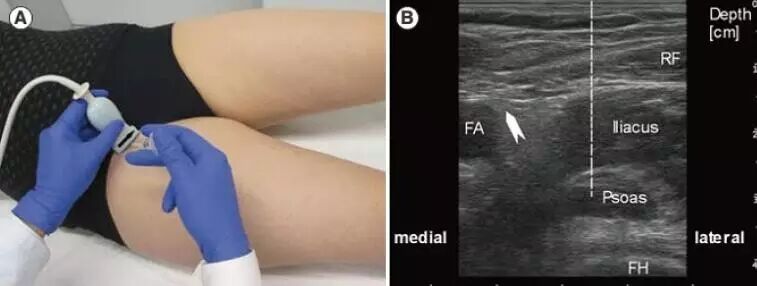

b. 下肢屈肌痉挛的BTX-A注射。下肢痉挛最常见的模式是膝关节伸展,踝关节跖屈;可注射腓肠肌和胫骨后肌。髂腰肌痉挛可引起髋关节屈曲,是下肢注射难度较高的肌肉,超声引导可为髂腰肌的BTX-A 注射提高便捷的定位方式。Westhoff 等对13 例髂腰肌痉挛的患者进行超声引导下BTX- 注射。选用 Dysport®,基础剂量为10 ~ 20 U/kg,极量为 500U/ 髋。患者仰卧位,使用 TSK-Supra0.8G注射器 ( 12cm长,TSK, Tochigi,  Japan ) 注射髂腰肌。超声探头为5 或7.5MHz,探头与股骨头平行,置于腹股沟处检查髂腰肌长轴( 如图4),超声成像( 如图5)。沿髂腰肌将探头向头端移动,于探头远端,朝向头端进针( 如图4)。

图4 超声引导下BTX-A注射髂腰肌,超声探头置放与进针点

图5 髂腰肌纵轴超声成像。(1)股骨头;(2)髋臼;(3)关节囊伴随着股骨头、股骨颈的轮廓;(4)髂腰肌在关节囊上方;(5)皮下脂肪